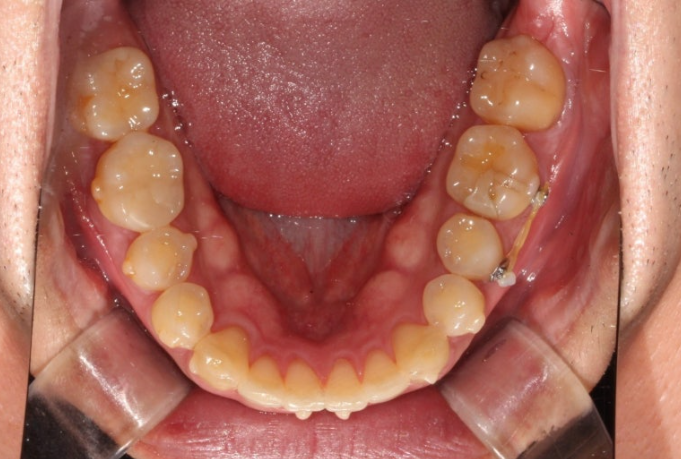

24년 12월부터 25년 4월까지 라이트 프로그램에서 허용하는 장치 14개 모두 낀 후 모습입니다.

25.04

중심선은 처음에 비해 많이 맞아졌고 여전히 약간의 불일치가 남아있습니다.

아래 작은어금니의 완벽한 회전을 위해서 고무를 걸 부가장치를 붙인채 치료를 진행했습니다.

가위교합의 빠른 해결을 위한 입천장의 교정용 나사도 썼습니다.

안으로 쓰러져 있던 큰어금니도 잘 세워졌고 가위교합도 해소가 되었습니다.

또 고무줄의 힘으로 아래 작은어금니 회정는 1차세트에서 대부분 개선이 됩니다.

중심선 일치, 미세공간 등 추가개선을 위해 추가장치 제작에 들어갑니다.